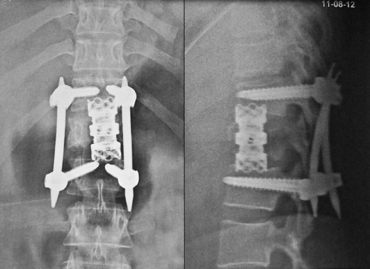

Fixation in fracture with complete paraplegia. It does not recover. Surgery is for better nursing care Physiotherapy and vocational rehabilitation